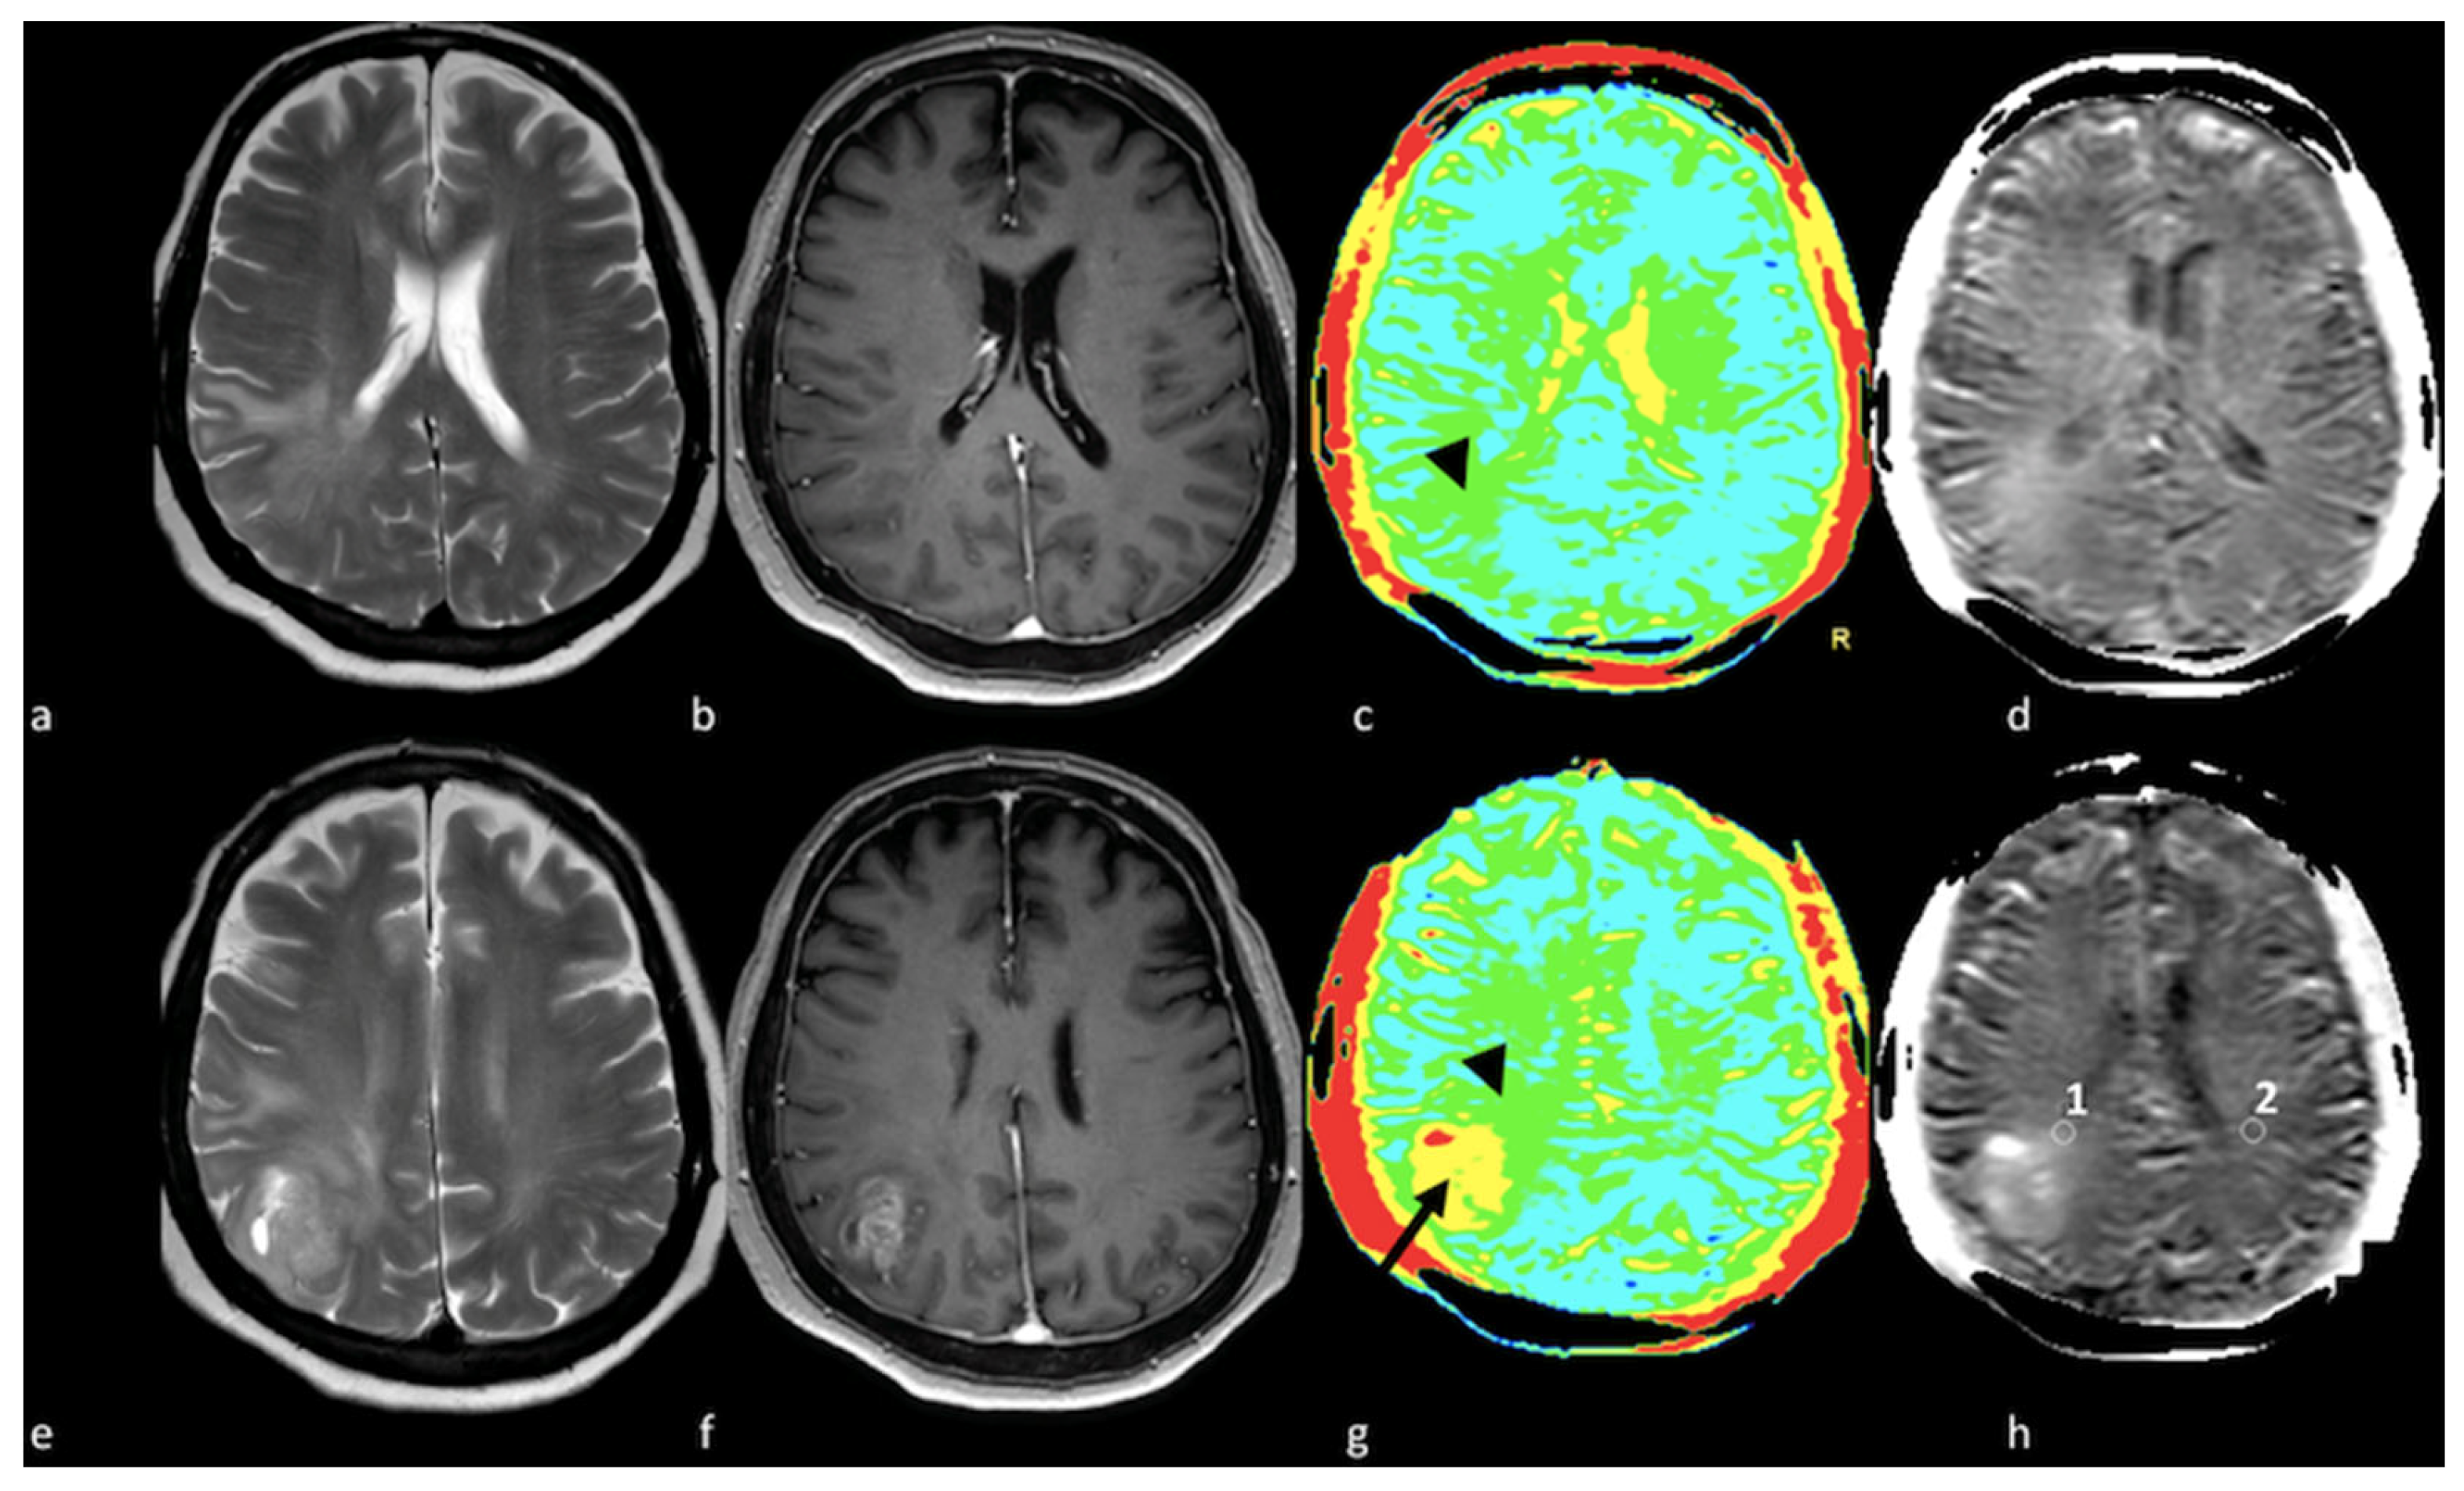

- Halshtok Neiman, O.; Sadetzki, S.; Chetrit, A.; Raskin, S.; Yaniv, G.; Hoffmann, C. Perfusion-weighted imaging of peritumoral edema can aid in the differential diagnosis of glioblastoma mulltiforme versus brain metastasis. Isr. Med. Assoc. J. 2013, 15, 103–105. [Google Scholar] [PubMed]

- Neska-Matuszewska, M.; Bladowska, J.; Sasiadek, M.; Zimny, A. Differentiation of glioblastoma multiforme, metastases and primary central nervous system lymphomas using multiparametric perfusion and diffusion MR imaging of a tumor core and a peritumoral zone-Searching for a practical approach. PLoS ONE 2018, 13, e0191341. [Google Scholar] [CrossRef]

- Askaner, K.; Rydelius, A.; Engelholm, S.; Knutsson, L.; Latt, J.; Abul-Kasim, K.; Sundgren, P.C. Differentiation between glioblastomas and brain metastases and regarding their primary site of malignancy using dynamic susceptibility contrast MRI at 3T. J. Neuroradiol. 2019, 46, 367–372. [Google Scholar] [CrossRef]

- Blasel, S.; Jurcoane, A.; Franz, K.; Morawe, G.; Pellikan, S.; Hattingen, E. Elevated peritumoural rCBV values as a mean to differentiate metastases from high-grade gliomas. Acta Neurochir. 2010, 152, 1893–1899. [Google Scholar] [CrossRef] [PubMed]

- Sunwoo, L.; Yun, T.J.; You, S.H.; Yoo, R.E.; Kang, K.M.; Choi, S.H.; Kim, J.H.; Sohn, C.H.; Park, S.W.; Jung, C.; et al. Differentiation of Glioblastoma from Brain Metastasis: Qualitative and Quantitative Analysis Using Arterial Spin Labeling MR Imaging. PLoS ONE 2016, 11, e0166662. [Google Scholar] [CrossRef] [PubMed]

- Lin, L.; Xue, Y.; Duan, Q.; Sun, B.; Lin, H.; Huang, X.; Chen, X. The role of cerebral blood flow gradient in peritumoral edema for differentiation of glioblastomas from solitary metastatic lesions. Oncotarget 2016, 7, 69051–69059. [Google Scholar] [CrossRef] [PubMed]